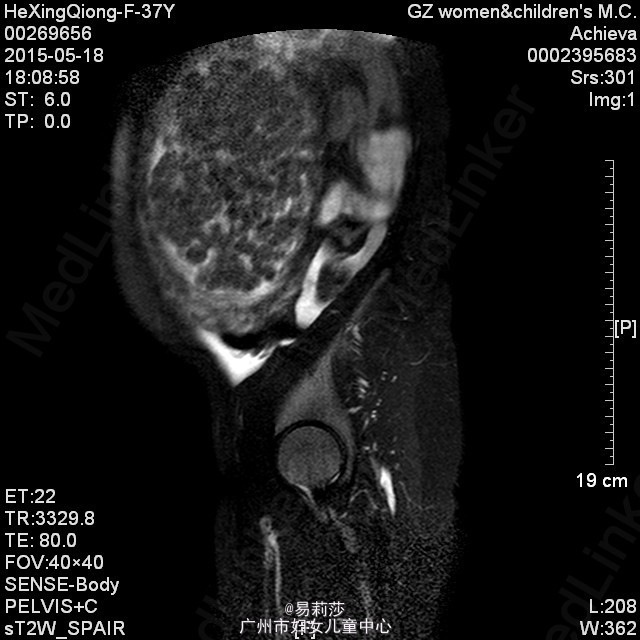

患者何××,女,G0P0,36岁,因“体检发现子宫肌瘤半年”于2015-06-23入院。患者平素月经规则,LMP:2015-06-12。患者于半年前体检时发现子宫肌瘤,未治疗。2月前,患者自觉腹部包块逐渐增大,2015-05-12彩超检查示:子宫前位,后壁见一实性低回声团,范围约125×193×192mm,边界尚清,明显外突,内回声欠均匀,宫腔线隐约可见,双侧附件因肿块遮挡,显示不清,CDFI:上述低回声团内见短棒及条索状血流信号,查血常规示:血红蛋白31g/L,拟“子宫平滑肌瘤”收入我科。入院后查贫血组合示缺铁,予输红细胞悬液6个单位,复查血色素81g/L,患者要求出院,此次再次入院要求手术治疗。查体:T36.2℃,P100次/分,R20次/分,BP132/74mmHg,神清,中度贫血外观,心肺听诊无异常,腹膨隆,宫底达剑突下1cm,无压痛、反跳痛。妇科检查:外阴发育正常,阴毛女性分布;阴道畅,分泌物色白,无异味;宫颈光滑,无肥大,无举痛及着色;宫体前位,增大,宫底达剑突下1cm,质硬,活动差,无压痛;双侧附件未扪及包块及压痛。 辅助检查:2015-06-24彩超检查示:胆囊息肉(胆固醇结晶),副脾,肝、胰、右肾未见明显异常回声,左肾下极异常回声团——畸胎瘤?,考虑来源左侧卵巢可能,与左肾关系密切,巨大子宫肌瘤,左侧卵巢显示不清,请进一步检查。MRI检查示:1.子宫左侧壁巨大实性肿块影,考虑巨大子宫肌瘤可能性大,子宫明显受压;2、左肾下方类圆形病变,考虑畸胎瘤可能性大;3、双侧腹膜后区主动脉、下腔动脉周围见不规则囊状影,考虑淋巴管扩张可能;4、盆腔少量积液。